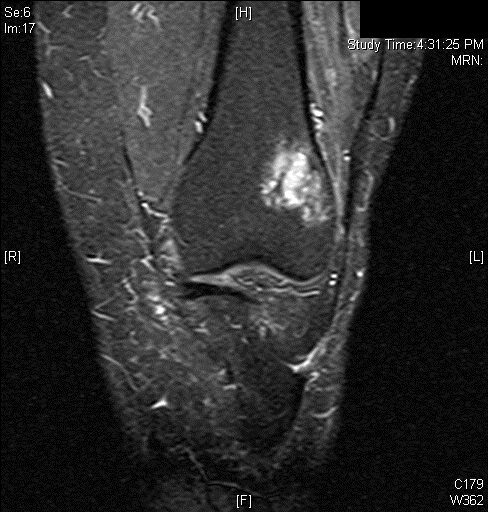

MRI

• MR Imaging, demonstrates intermediate to hypointense signal on T1-weighted images (Fig. 4 & 5) and hyperintensity on T2-weighted images (Fig. 6 & 7).

Fig. 4

Fig. 5

Fig. 4 & 5: MR Imaging. Axial (Fig. 4) and Coronal (Fig. 5) T1 weighted image demonstrates a well-defined T1 hypointense mass within the femur with a more hypointense border corresponding to the sclerosis noted on the CT

Fig. 6

Fig. 7

Fig. 6 & 7: MR Imaging. Axial (Fig. 6) and Coronal (Fig. 7) T2 fat saturated image demonstrating T2 hyperintense lesion within the lateral supracondylar femur with a small amount of surrounding bone marrow edema.